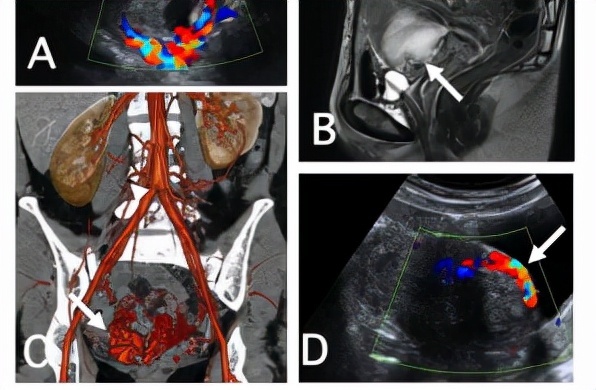

禍不單行!再次瘢痕妊娠這種懷孕真的可能分分鐘“要命”!

隨著二胎、三胎的開(kāi)放,婦科接診的子宮瘢痕妊娠患者明顯增多。但很多人對(duì)瘢痕妊娠的認(rèn)識(shí)還不夠清晰,不知道它的風(fēng)險(xiǎn)到底有多大。明星陳浩民的老婆5年4次剖宮產(chǎn)都安然無(wú)恙,不禁讓普通老百姓放松了警惕,以為剖宮產(chǎn)沒(méi)什么大不了的。但殊不知,婦產(chǎn)科醫(yī)生們真是替她的主刀醫(yī)師和她自己都捏了一把汗。什么是子宮疤痕妊娠?剖宮產(chǎn)瘢痕妊娠(CSP)是指孕產(chǎn)婦的受精卵或孕囊著床于前次剖宮產(chǎn)切口瘢痕處,是剖宮產(chǎn)術(shù)后遠(yuǎn)期并發(fā)癥之一,可導(dǎo)致胎盤植入、子宮破裂、大量出血、嚴(yán)重者危及生命。文獻(xiàn)報(bào)道剖宮產(chǎn)瘢痕妊娠在早孕女性中的患病率約為1:1800,CPS占異位妊娠合并剖宮產(chǎn)術(shù)史患者比例為6.1%。再次瘢痕妊娠,風(fēng)險(xiǎn)不可小覷隨著剖宮產(chǎn)產(chǎn)婦數(shù)量上升,瘢痕子宮再次妊娠產(chǎn)婦也逐漸增多,而剖宮產(chǎn)術(shù)后再次妊娠女性CPS發(fā)病率為0.15%。此時(shí),治療難度加大,并發(fā)癥風(fēng)險(xiǎn)明顯增多。30歲的張女士(化名),在2019年的時(shí)候已經(jīng)經(jīng)歷了剖宮產(chǎn)2次,人工流產(chǎn)2次,因“停經(jīng)48天,清宮術(shù)后陰道出血4天”,就診于鹽城市第一人民醫(yī)院,門診擬“瘢痕妊娠”入院。當(dāng)時(shí)B超提示宮腔下段瘢痕處見(jiàn)1510mm混合回聲,探及明顯血流。入院后進(jìn)行了腹腔鏡下雙側(cè)子宮動(dòng)脈上行支結(jié)扎+盆腔粘連松解術(shù)+清宮術(shù)。手術(shù)過(guò)程順利,出血約50ml。就在不久之后,距離前次瘢痕妊娠手術(shù)僅9月余的時(shí)間,張女士又因“停經(jīng)53天,陰道出血2天”入院,B超見(jiàn)子宮切口處見(jiàn)大小約127mm的妊娠囊,凸向子宮切口方向生長(zhǎng),提示再次瘢痕妊娠。我院婦產(chǎn)科陳小平主任介紹到,瘢痕妊娠的治療一般包括藥物保守治療后,輔以B超監(jiān)視下的清宮術(shù);開(kāi)腹或腹腔鏡下局部病灶切除術(shù);以及介入治療,即子宮動(dòng)脈栓塞術(shù)后輔以B超監(jiān)視下清宮術(shù)。腹腔鏡手術(shù)治療亦適用首次及再次瘢痕子宮治療。腹腔鏡手術(shù)治療有以下優(yōu)勢(shì):-出血少:阻斷子宮動(dòng)脈上行支,就能阻斷子宮體部血供主干,減少清宮時(shí)出血。-更安全:腹腔鏡觀察下行清宮術(shù),若出現(xiàn)穿孔亦可及時(shí)修補(bǔ),并可以對(duì)瘢痕處進(jìn)行加固。-預(yù)后佳:阻斷子宮動(dòng)脈上行支可以很快建立側(cè)支循環(huán),子宮不會(huì)缺血壞死,亦不影響血運(yùn)及月經(jīng)來(lái)潮。再次瘢痕妊娠后,陳小平主任團(tuán)隊(duì)對(duì)患者進(jìn)行了腹腔鏡下雙側(cè)輸卵管結(jié)扎+子宮動(dòng)脈上行結(jié)扎+清宮術(shù)。術(shù)中出血少,術(shù)后安返病房,術(shù)后HCG下降迅速,恢復(fù)滿意。該如何預(yù)防瘢痕妊娠?1、降低剖宮產(chǎn)率和侵入性子宮操作由于CSP絕大多數(shù)發(fā)生于剖宮產(chǎn)術(shù)后,因此需要醫(yī)務(wù)人員充分與患者溝通,宣傳自然分娩,并積極開(kāi)展導(dǎo)樂(lè)、分娩鎮(zhèn)痛等服務(wù)改善自然分娩體驗(yàn),嚴(yán)格把握手術(shù)指征,降低剖宮產(chǎn)率避免無(wú)指征剖宮產(chǎn)。2、嚴(yán)格避孕加強(qiáng)計(jì)劃生育工作,針對(duì)不同人群開(kāi)展針對(duì)性避孕宣傳減少人工流產(chǎn)等宮腔侵入性操作,從而減少子宮瘢痕及子宮內(nèi)膜損傷的發(fā)生。子宮手術(shù)后如患者無(wú)妊娠需求,應(yīng)建議患者嚴(yán)格避孕,并提供具體可行的避孕指導(dǎo),避免再次妊娠。如患者有妊娠需求,再次妊娠前評(píng)估子宮瘢痕愈合情況并于早孕期行超聲明確胎囊位置。醫(yī)生在此提醒,有剖宮產(chǎn)史的婦女再次妊娠,應(yīng)警惕子宮瘢痕妊娠的可能,一旦停經(jīng)后出現(xiàn)陰道不規(guī)則流血,宜早期行超聲或MRI檢查,若確診為子宮疤痕妊娠,要盡早終止妊娠。